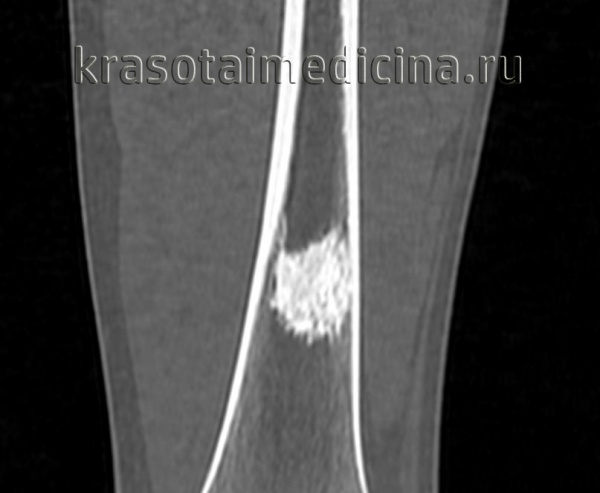

КТ левого бедра. Объемное образование (оссифицированная энхондрома) в нижней трети диафиза бедренной кости.